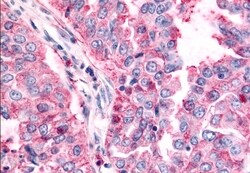

TAOK1 Polyclonal Antibody for IHC (P)

| Immunohistochemistry (Paraffin) | |